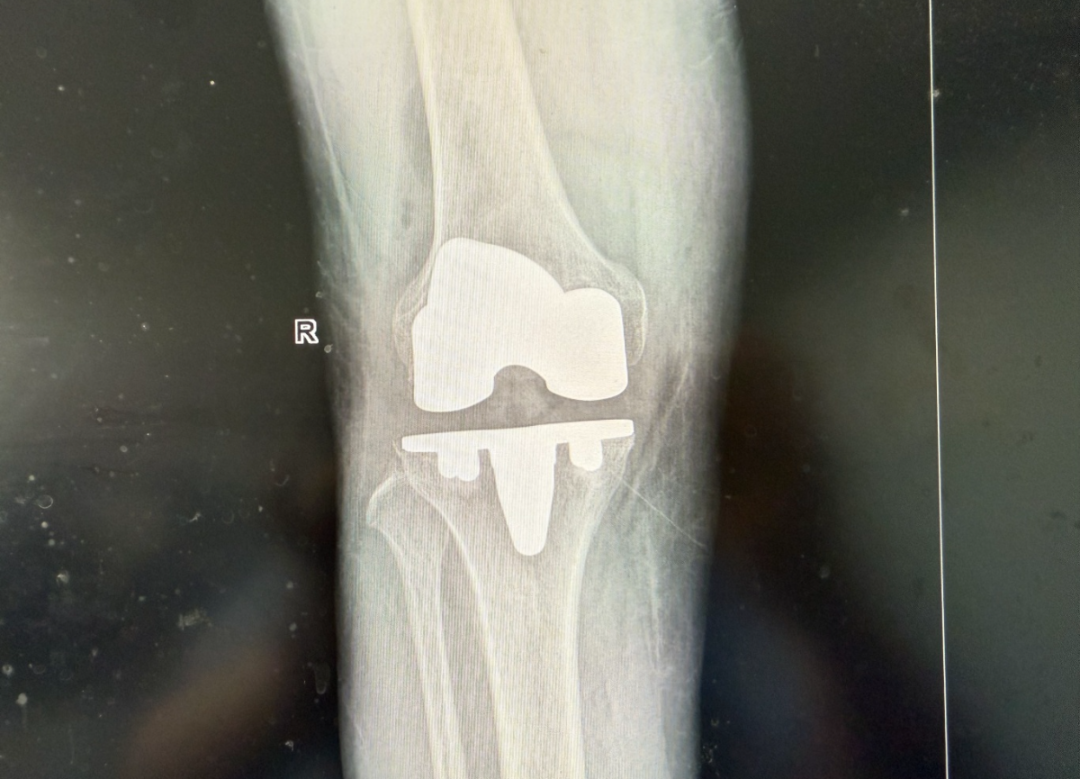

手术当日,在尹主任的带领下,骨科团队凭借精湛技术和默契配合,成功为于大叔实施了这台意义非凡的生物型全膝关节置换手术。手术过程顺利,患者生命体征平稳。

术后康复是手术成功的关键一环。在骨科医护团队及驻科康复治疗师的精心护理及专业指导下,于大叔的恢复速度令人欣喜。术后第一天,他便在助行器的辅助下,于病房内迈出了坚实的第一步。久违的笑容,重新绽放在他的脸上。“终于能站起来了,感觉太好了!”于大叔激动地说。

尹绍猛表示,这例手术的成功,不仅在于解除了患者当下的病痛,更在于为他的长远生活质量提供了坚实保障。对于50岁左右甚至更年轻的严重膝关节炎患者,我们不仅要解决“现在能走”的问题,更要考虑“未来几十年还能走得好”。生物型膝关节置换技术通过促进骨组织与假体的直接融合,大大提高了假体的长期稳定性,有效规避了骨水泥老化、松动带来的远期翻修风险,这是我们骨科技术发展的重要方向,也是我们为患者提供更精准、更个体化、更具前瞻性治疗方案的体现。

假体表面经3D打印技术形成200-600微米级仿生孔隙,配合羟基磷灰石生物活性涂层,可诱导患者自体骨细胞长入假体孔隙,实现骨骼与假体的生物性融合,有效避免传统骨水泥可能出现的松动、下沉等问题,显著延长假体使用寿命。

采用人工智能术前规划系统,通过CT三维建模定制个体化截骨导板,实现±0.5mm级精准截骨。相较传统手术需大量磨削骨骼以适配骨水泥层,生物型系统可多保留15%-20%自体骨量,为未来可能的翻修手术预留宝贵骨储备。

生物固定方式无需等待骨水泥凝固,术后6小时即可在支具保护下开展步态训练。临床数据显示,患者术后3天自主行走距离较传统术式提升40%,关节活动度提前2周达到120°功能角度。